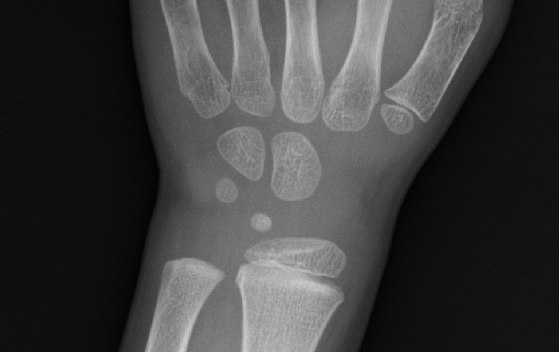

負傷したのは金曜の夕方で、土曜は痛がってはいたがサッカーもしてプールにも行ったので、それほど心配してなかったが、レントゲンを撮ってみると、骨が少しだけ折れてる(ひび?)らしい。

分かりにくいかもしれないが、レントゲンの写真をもらったので載せておこう。